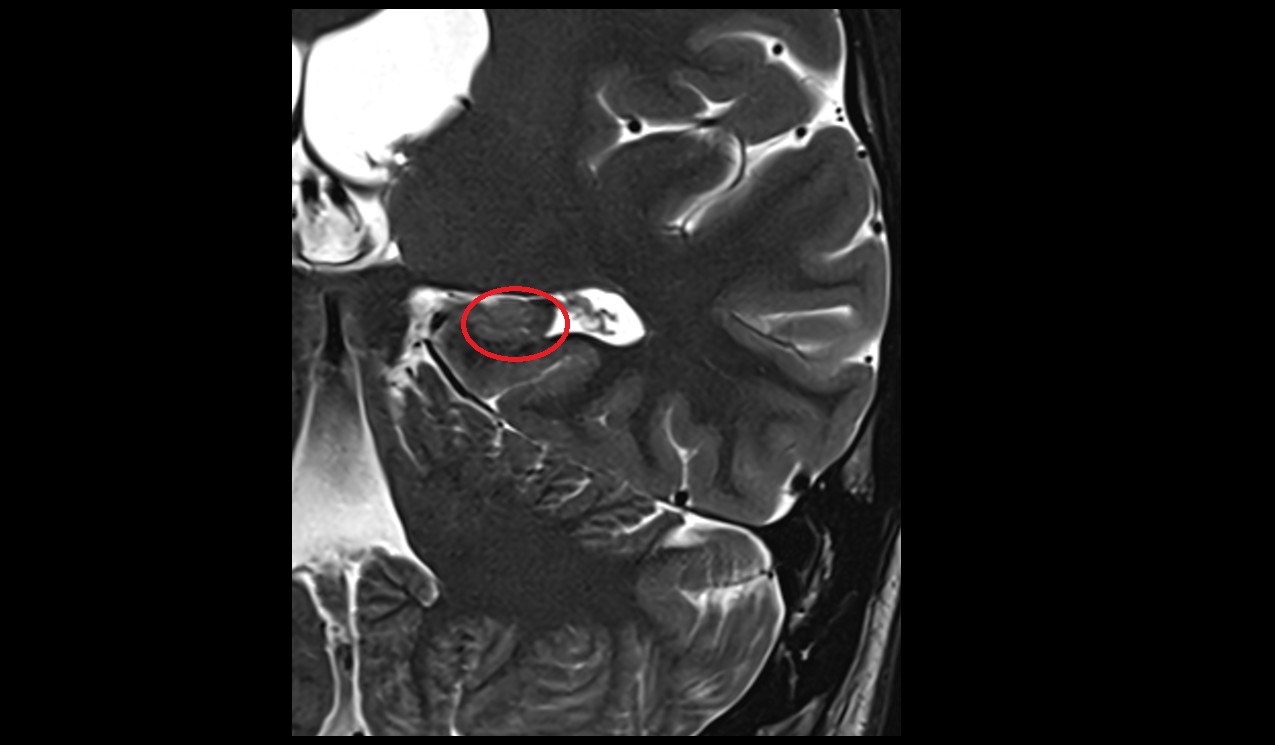

- Hippocampal head

- Head of hippocampus